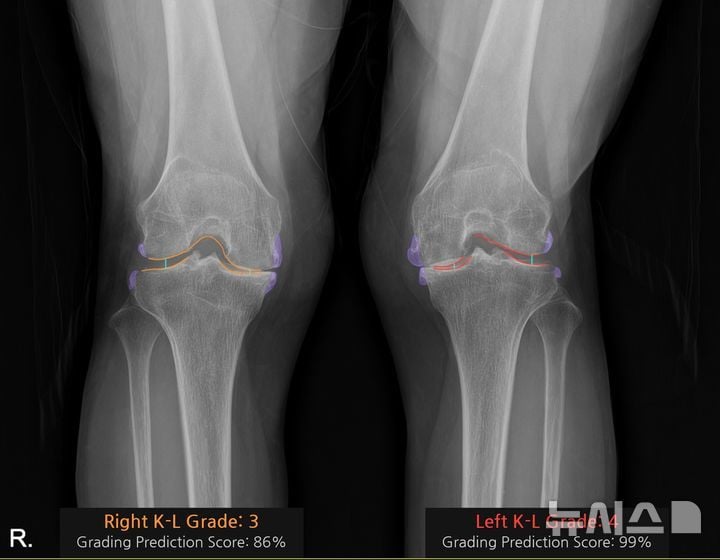

AI 기반 무릎 관절염 진단 기술이 국내 대형병원의 현장 진료에 본격 도입되며 정형외과 의료서비스의 패러다임을 바꾸고 있다. 중앙대병원이 최근 상용화한 AI 진단보조 솔루션 ‘코네보 코아’는 환자의 무릎 엑스레이(X-ray) 영상을 불과 10초 만에 분석, 관절염 등급을 색상별로 시각화해주는 혁신적 도구다. 의료진과 환자 모두가 이미지에서 손상 부위와 악화 정도를 즉각적으로 파악할 수 있어, 진료 과정의 효율성과 만족도가 동시에 높아지고 있다. 업계에서는 이번 도입을 ‘AI 의료 영상 경쟁의 분기점’으로 보고 있다.

코네보 코아의 기술적 핵심은 단순 이미지 분석이 아니라, 관절 간격·골극(뼈 돌기) 형태·연골 손상 패턴 등 관절염 진단의 주요 지표를 AI가 학습하고, 국제 표준 진단 기준(Kellgren-Lawrence 등급)에 따라 자동 분류하는 데 있다. 의료진마다 차이를 보일 수 있는 등급 평가의 일관성을 높이고, 초기 단계(Grade 0~1) 병변의 조기 발견까지 지원하는 것이 기존 판독 방식과의 차별점이다. 실제로 김수진 중앙대병원 영상의학과 교수는 “의사마다 관절염 등급 평가가 달랐던 문제를 AI가 객관적으로 바로잡아, 진단 신뢰도가 크게 올랐다”고 설명했다.

진단 효율과 환자 소통의 개선 효과도 뚜렷하다. 김성환 중앙대병원 정형외과 교수는 “AI가 관절 상태 악화 부위를 색상으로 시각화해 환자도 자신의 상태와 치료 방향을 쉽게 이해한다”며, “설명 도구로서 현장 만족도가 높다”고 말했다. 특히, 영상 전문의가 부족한 1차 진료기관에서는 PACS 연동형 AI 판독시스템이 의료 현장의 진단 편차를 줄이고, 지방·고령층 환자의 진료 경험을 높이는 역할이 기대된다.